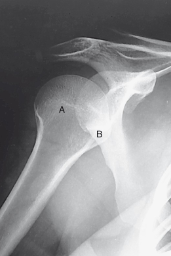

without labeling, this is the anatomy of what kind of x-ray? (projection and body part)

scapular Y lateral

label 1-7 accordingly

1. AC joint

2. Acromion

3. Scapular spine

4. Humeral head

5. Body of scapula (superimposed over

humerus)

6. Clavicle

7. Coracoid process